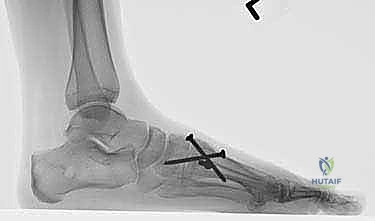

بعد التأكد من المحاذاة المثالية، يتم تثبيت العظام بشكل دائم. يستخدم الأستاذ الدكتور محمد هطيف أحدث التقنيات العالمية في التثبيت، والتي تشمل عادة مسامير تيتانيوم متقاطعة (Crossed Screws) أو شريحة معدنية متخصصة مع مسامير (Plating System) لضمان أقصى درجات الثبات والضغط بين العظمتين، مما يسرع من عملية الالتئام.

- المتابعة الإشعاعية: يتم إجراء أشعة سينية للتأكد من بدء التحام العظام.

- تحمل الوزن: إذا كانت الأشعة مطمئنة، يُسمح بالانتقال التدريجي لتحميل الوزن الكامل أثناء ارتداء الحذاء الطبي، ثم الانتقال لاحقاً إلى حذاء رياضي واسع ومريح.